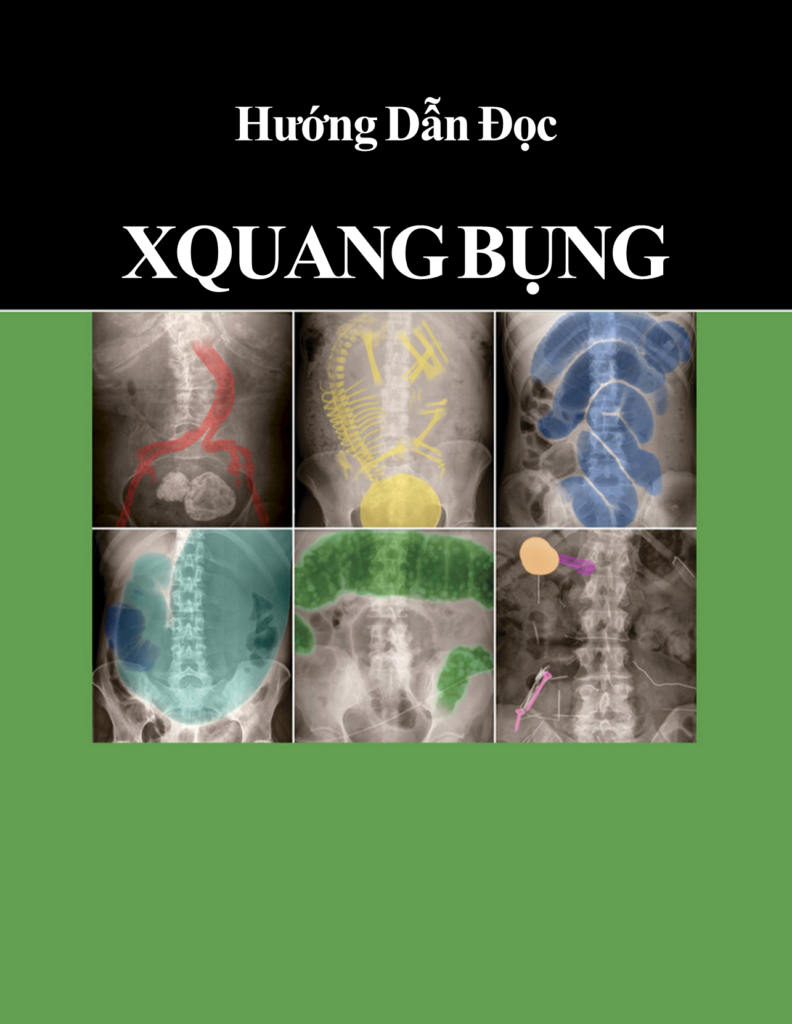

Hôm nay, Trang vừa sưu tầm được một tài liệu hay về chẩn đoán hình ảnh nên muốn chia sẻ đến các bạn để chúng ta cùng nhau tham khảo nhé. Tài liệu “Hướng Dẫn Đọc X-Quang Bụng” là một tài liệu hay về cách tiếp cận các phim X-Quang bụng cơ bản. Tài liệu […]